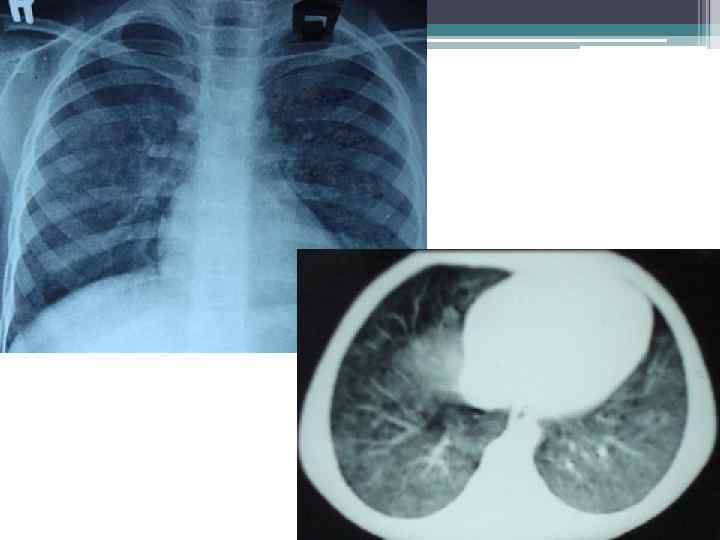

На рентгенограмме: мелкосетчатая диффузная деформация легочного рисунка, обусловленная уплотнением интерстициальн ой ткани легких, множественные рассеянные мелкие мономорфные очаговые тени.

Особенностью рентгенологически выявляемых изменений при ИГЛ является быстрое обратное развитие очагов затемнения. В ряде случаев на рентгенограммах грудной клетки отмечаются рассеянные мелкие тени в обоих легких, что служит причиной ошибочной диагностики милиарного туберкулеза легких. Изменения в легких, выявляемые при рентгенографии могут варьировать в широких пределах: от небольших инфильтратов до массивных тенеобразований, сопровождающихся ателектазами, эмфиземой и реакцией со стороны лимфатических узлов корней легких.